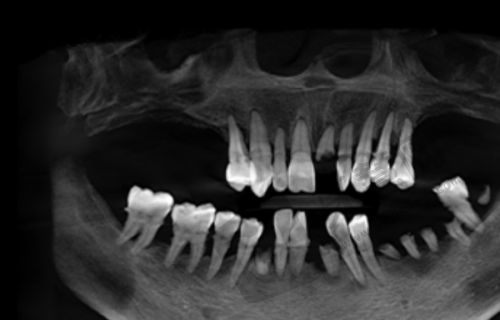

科室与团队:北京欢乐知春路口腔门诊部成立于2015年,具有一定规模,设有口腔科、医学影像科等科室,能满足患者多方面的口腔医疗需求。拥有经验多、技术不错的专精医生团队。

辐射安心:2025年6月9日,北京市海淀区生态环境局向其颁发辐射安心许可证(京环辐证[F0613]),许可内容为使用Ⅲ类射线装置,说明门诊部在使用相关射线装置时,符合国内的安心标准和要求,能够保护患者和医护人员的安心。